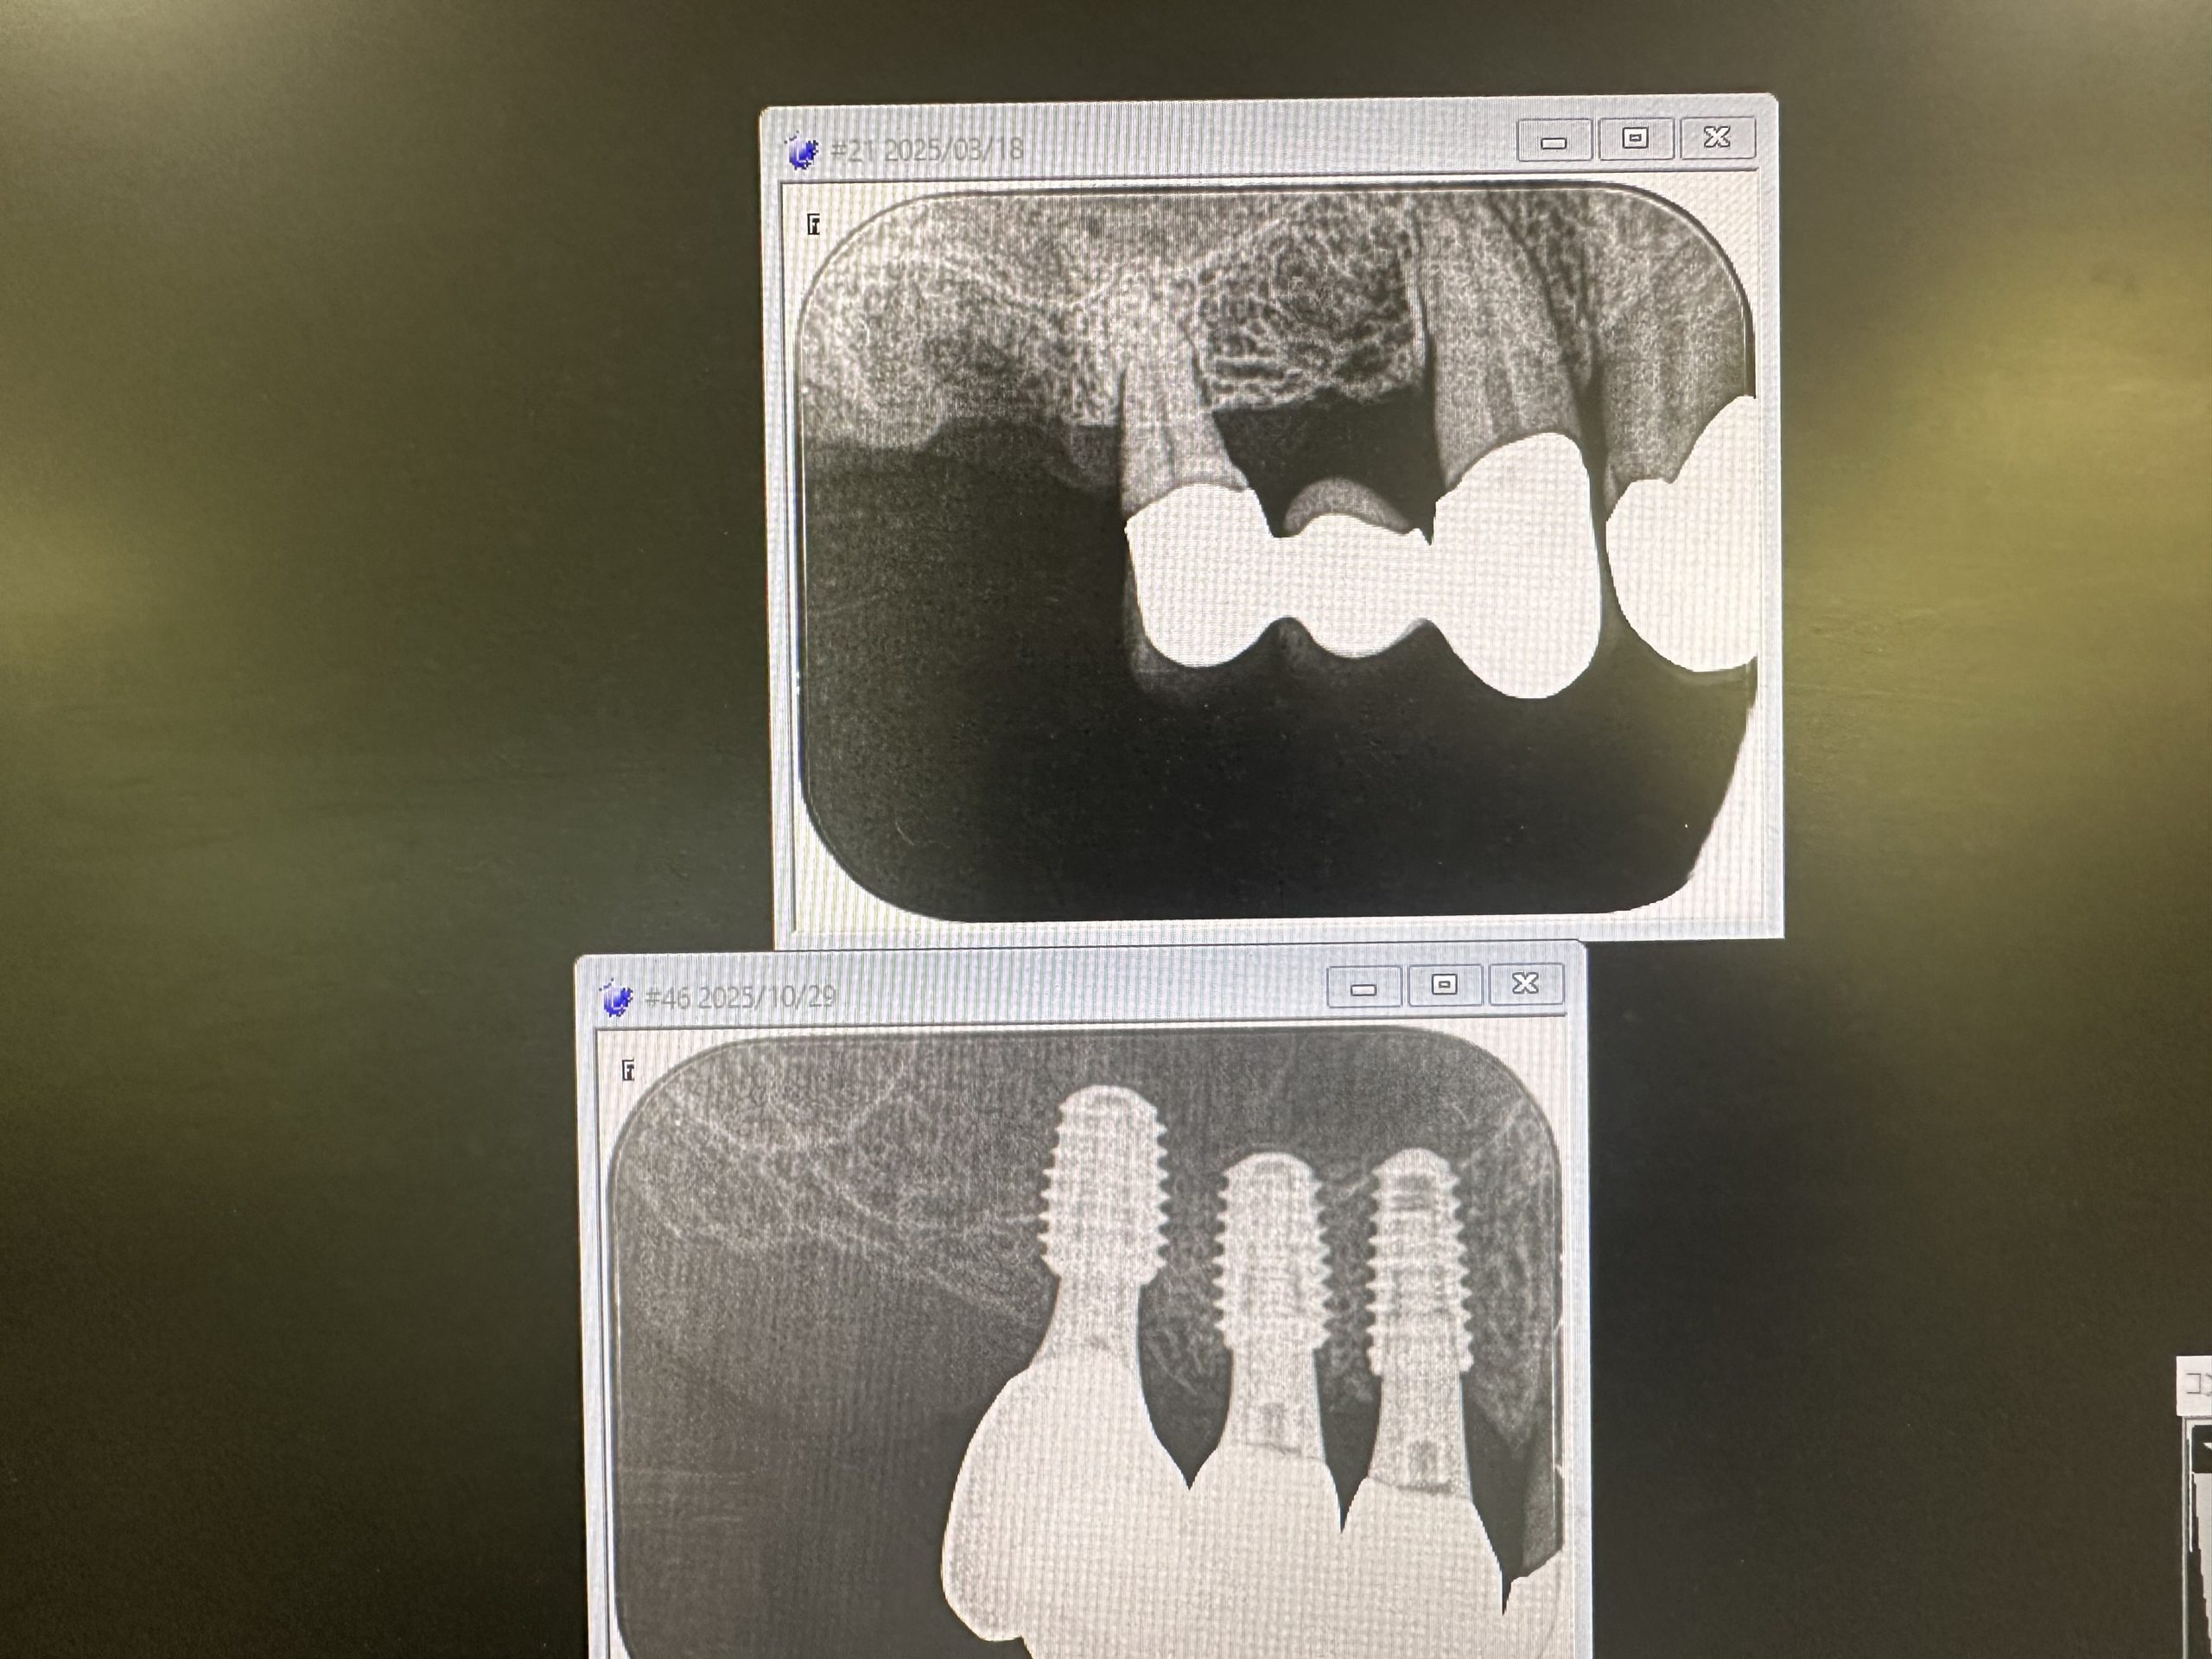

今年5月オペ、6番は残存骨2から3ミリ程度での、ソケットリフトデンサーバーによるリフト

4.5番は6wで仮歯装着、しかし6番は5ヶ月近くかかったが、本日最終補綴物セット